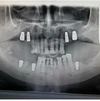

Implant tedavisi